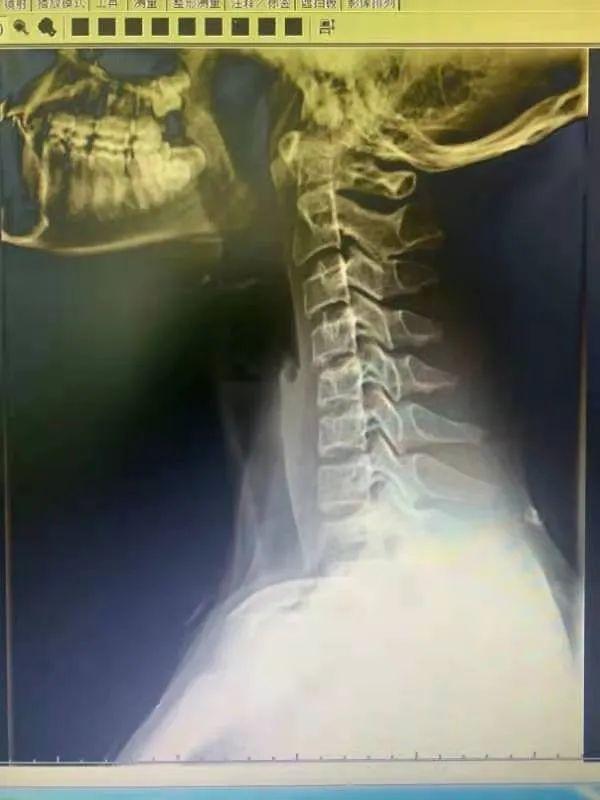

正常(颈曲凸向前)

颈部生理曲度变直